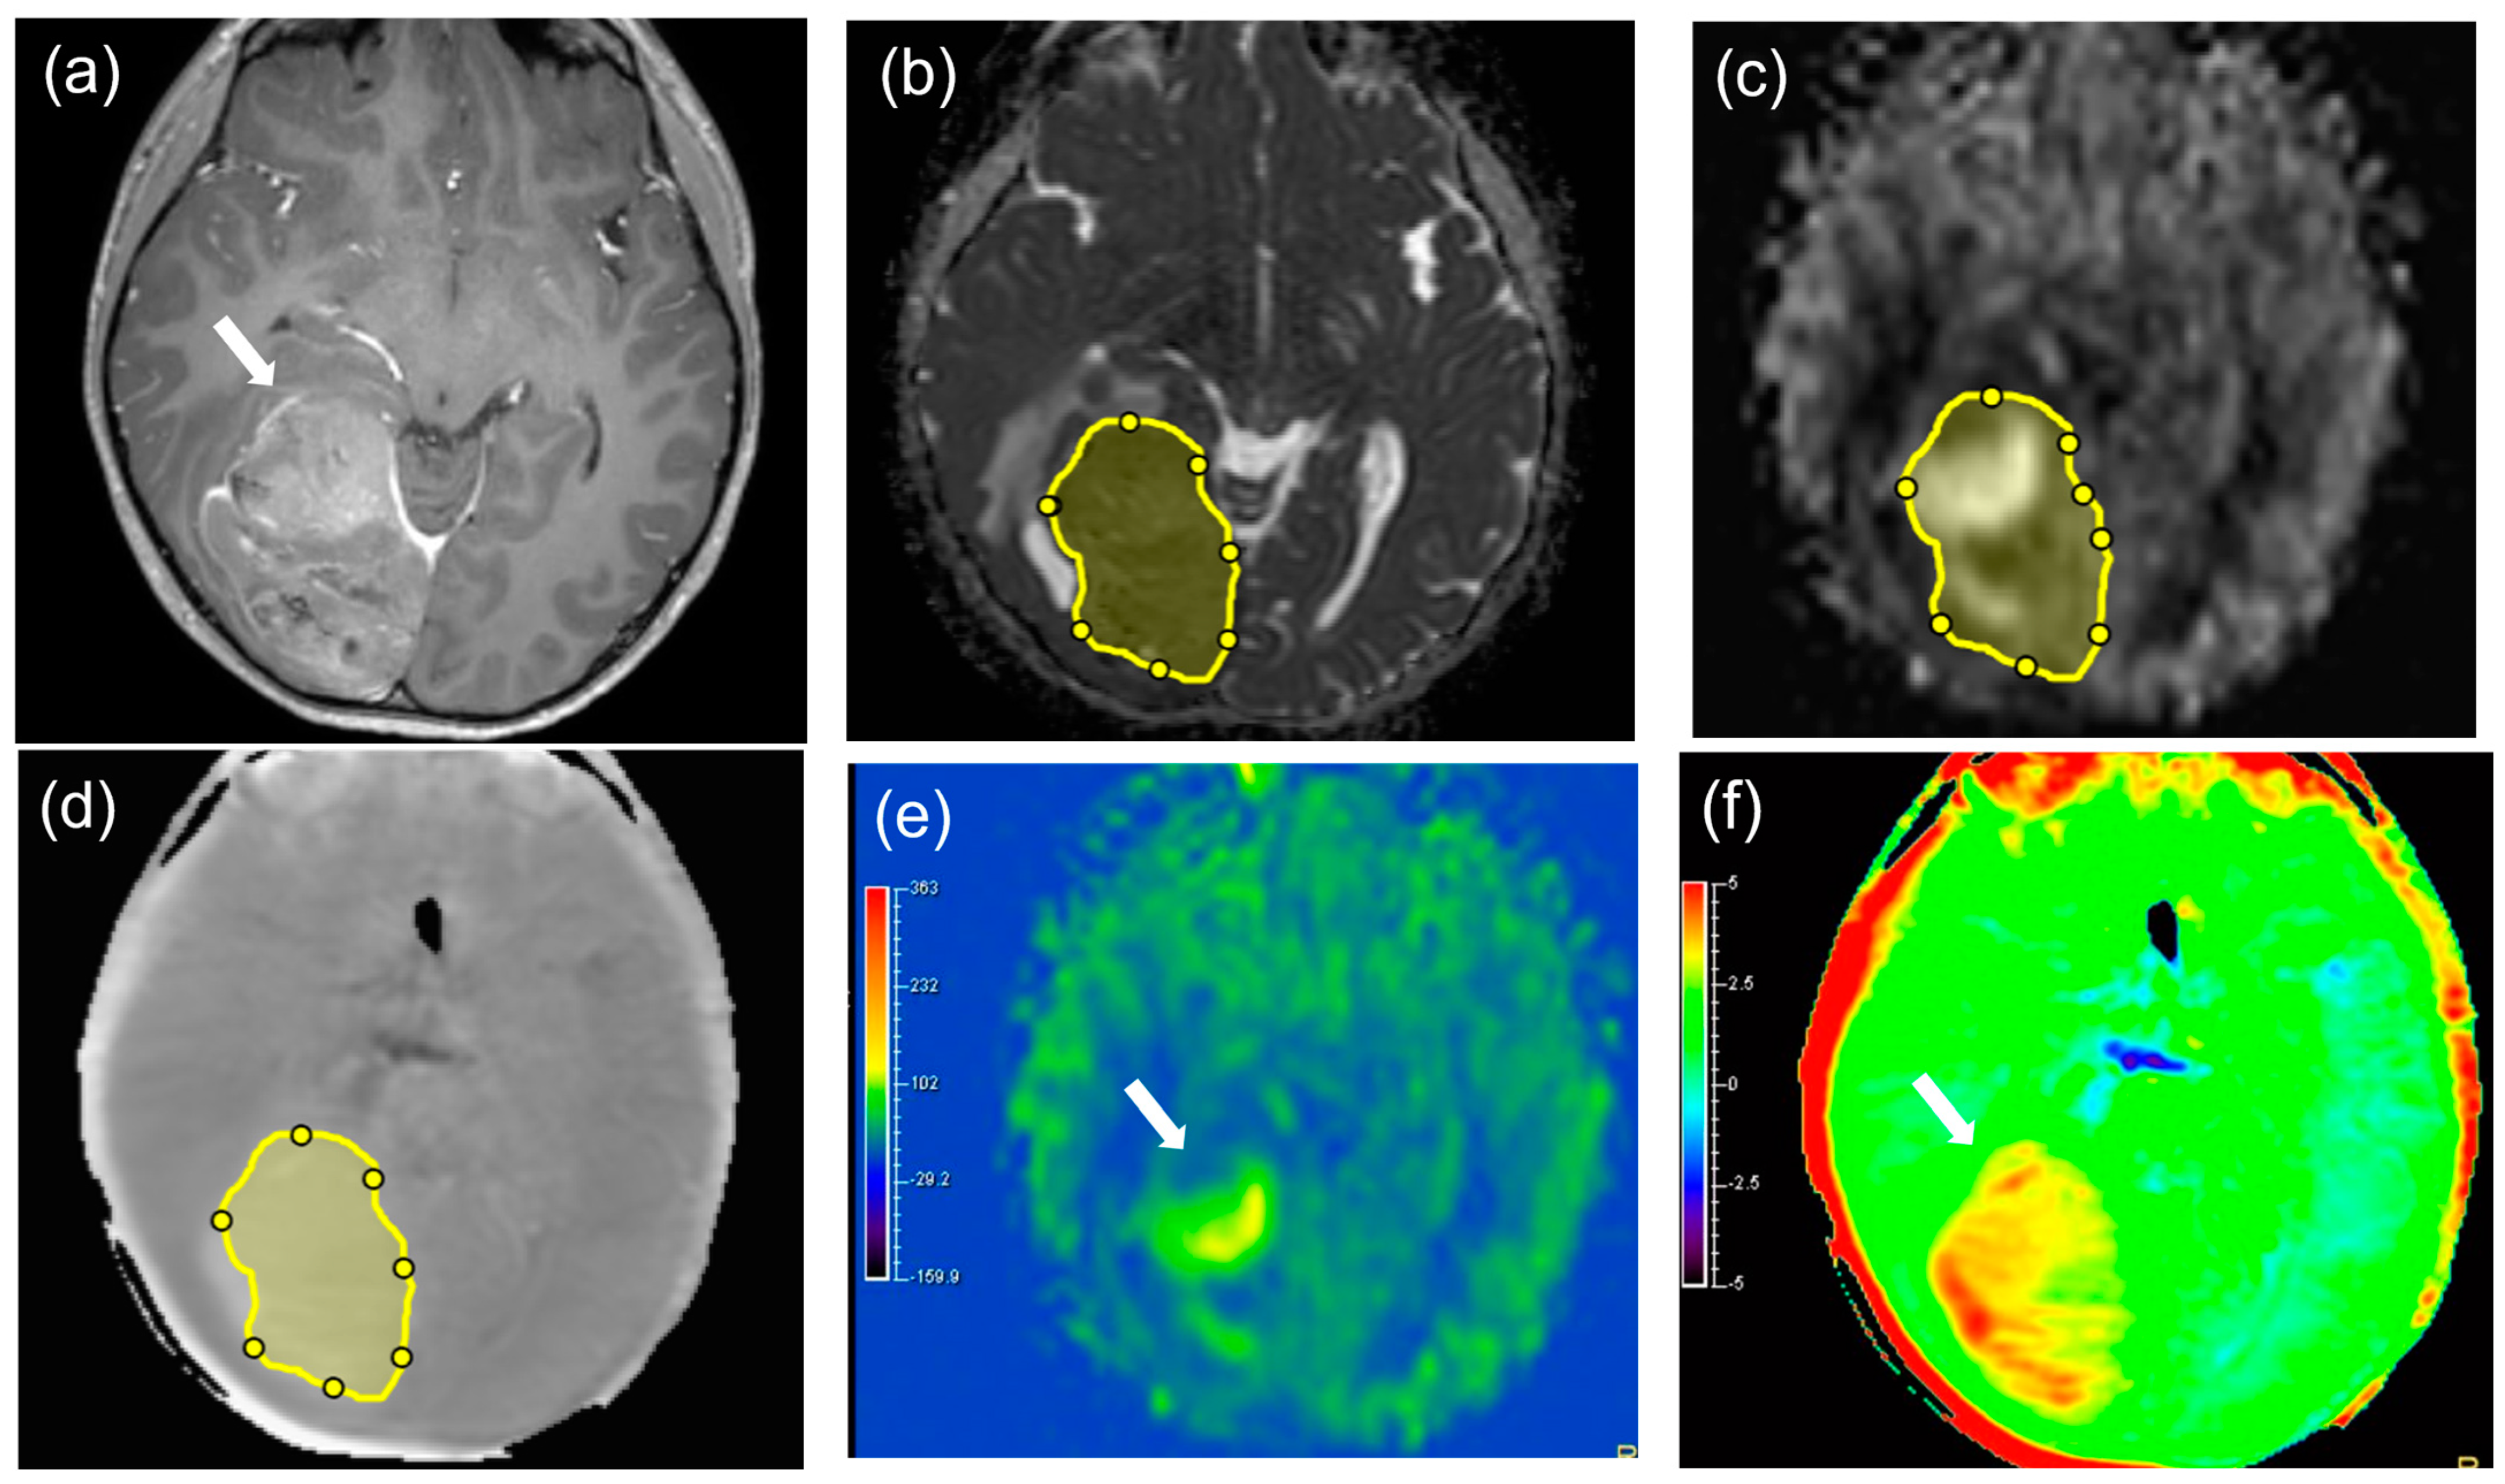

2.3. Image Analysis

3. Results

3.3. Comparisons of APT, TBF, and ADC Parameters between MTs and BTs

3.4. Diagnostic Performance for Differentiating MTs from BTs

4. Discussion